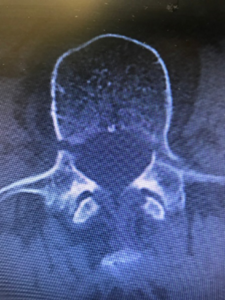

CTではさらに分離部が確認しやすく、進行度合い(病期)や分離部の骨癒合の経過を判断する目的に行います。

腰椎分離症の病期は、椎弓にひびが入った状態の初期、分離が進んでいく進行期、完全に分離した終末期(偽関節型)という3段階に分類できます。